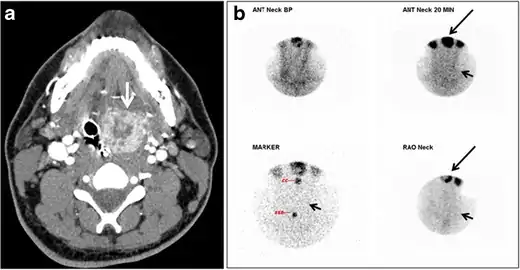

Thyroid scanning with technetium-99 m (Tc99m) plays an important role in detecting orthotopic and ectopic thyroid tissue. Both CT scans and US can help detect ectopic tissue when a lesion demonstrates imaging and enhancement characteristics of thyroid tissue. The absence of normally sited thyroid gland in US and CT scans also supports the diagnosis. In addition, US can guide FNA for cytological confirmation of a thyroid lesion. Ectopic thyroid tissue appears as a well-circumscribed, homogeneous, highly attenuating mass relative to adjacent muscles. Normally, it enhances avidly following the administration of iodinated contrast.[1]

Ectopic thyroid tissue may be detected in the tongue near the foramen cecum (90%) and along the midline between the thyroid isthmus and posterior tongue, lateral neck, mediastinum, and oral cavity. The most frequent location is the base of the tongue (Figs. 16, 1717 and and18).18). In 70% of cases, the ectopic thyroid is the only functional thyroid tissue present in the body (Fig. 18).[1]

Ectopic thyroid tissue lateral to the orthotopic midline location is rare. The exact anatomical definition of this rare entity is debated in the literature. To avoid confusion, some authors define a lateral neck ectopic thyroid as any thyroid tissue superficial to the strap muscles with no midline continuity. The majority of lateral thyroid ectopia cases have been reported as lesions closely related to the strap muscles. There are few reported cases of ectopic lateral thyroid tissue in the submandibular region, jugulodigastric region, or within the parotid gland substance (Fig. 17).[1]